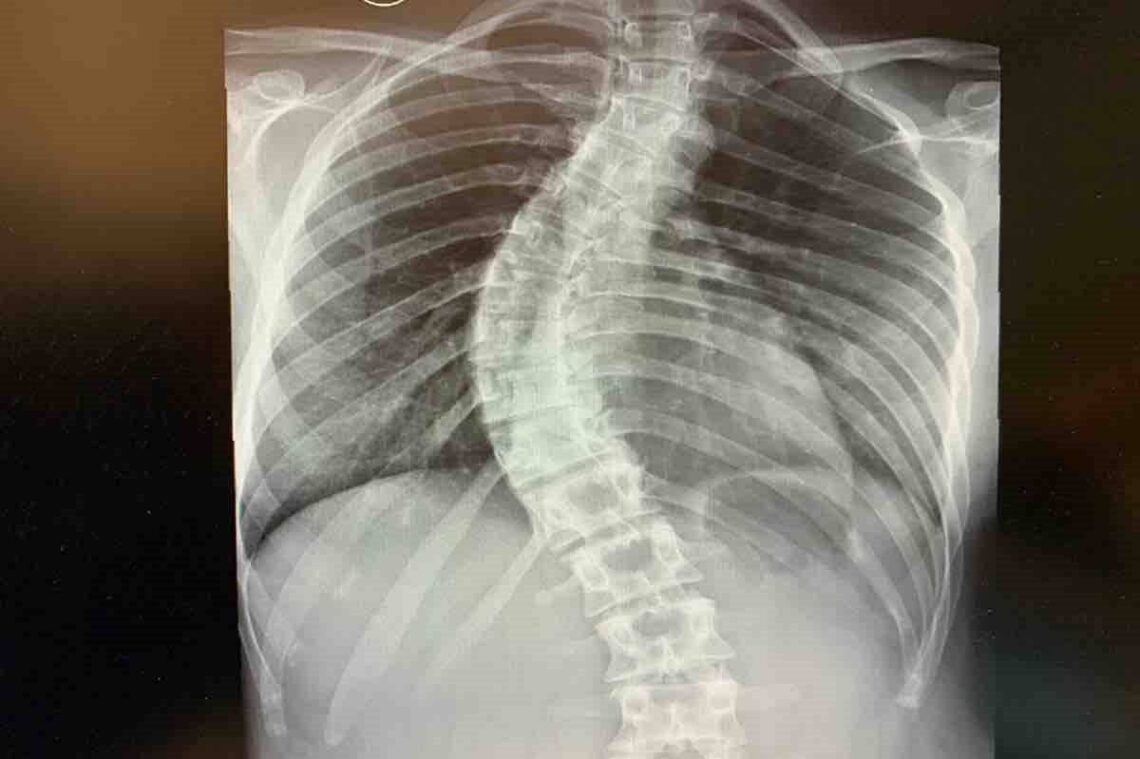

«Soy monitora de actividades dirigidas. A los 14 años empecé con dolores de espalda y hace más o menos un año empezó a dolerme fuertemente la lumbar. Evidentemente, mi curvatura había ido a más», explica la joven, que añade que la fisioterapia ya no consiguen aliviarla. El problema ya no es solo la curvatura de la columna, sino que va más allá, ya que sus costillas «están rotadas», como señala, lo que implica que sus pulmones queden oprimidos y su capacidad respiratoria disminuya.

Recientemente, López ha encontrado una clínica privada que emplea «un método totalmente distinto» y «mucho menos invasivo» que el habitual. Se llama método ASC, que usa una cuerda como método de corrección de la desviación de la columna y ofrece, entre otras cuestiones, una «total movilidad y una rápida recuperación». Sin embargo, se trata de una costosa intervención cuyos gastos, que ascienden a más de 53 mil euros, no cubre la sanidad pública y su familia no puede costearlos.